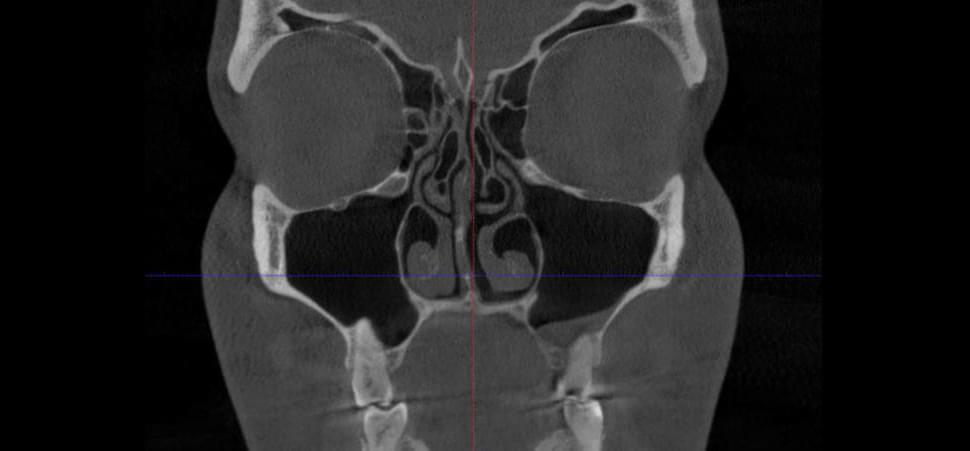

CBCT Maxilofaciální diagnostika